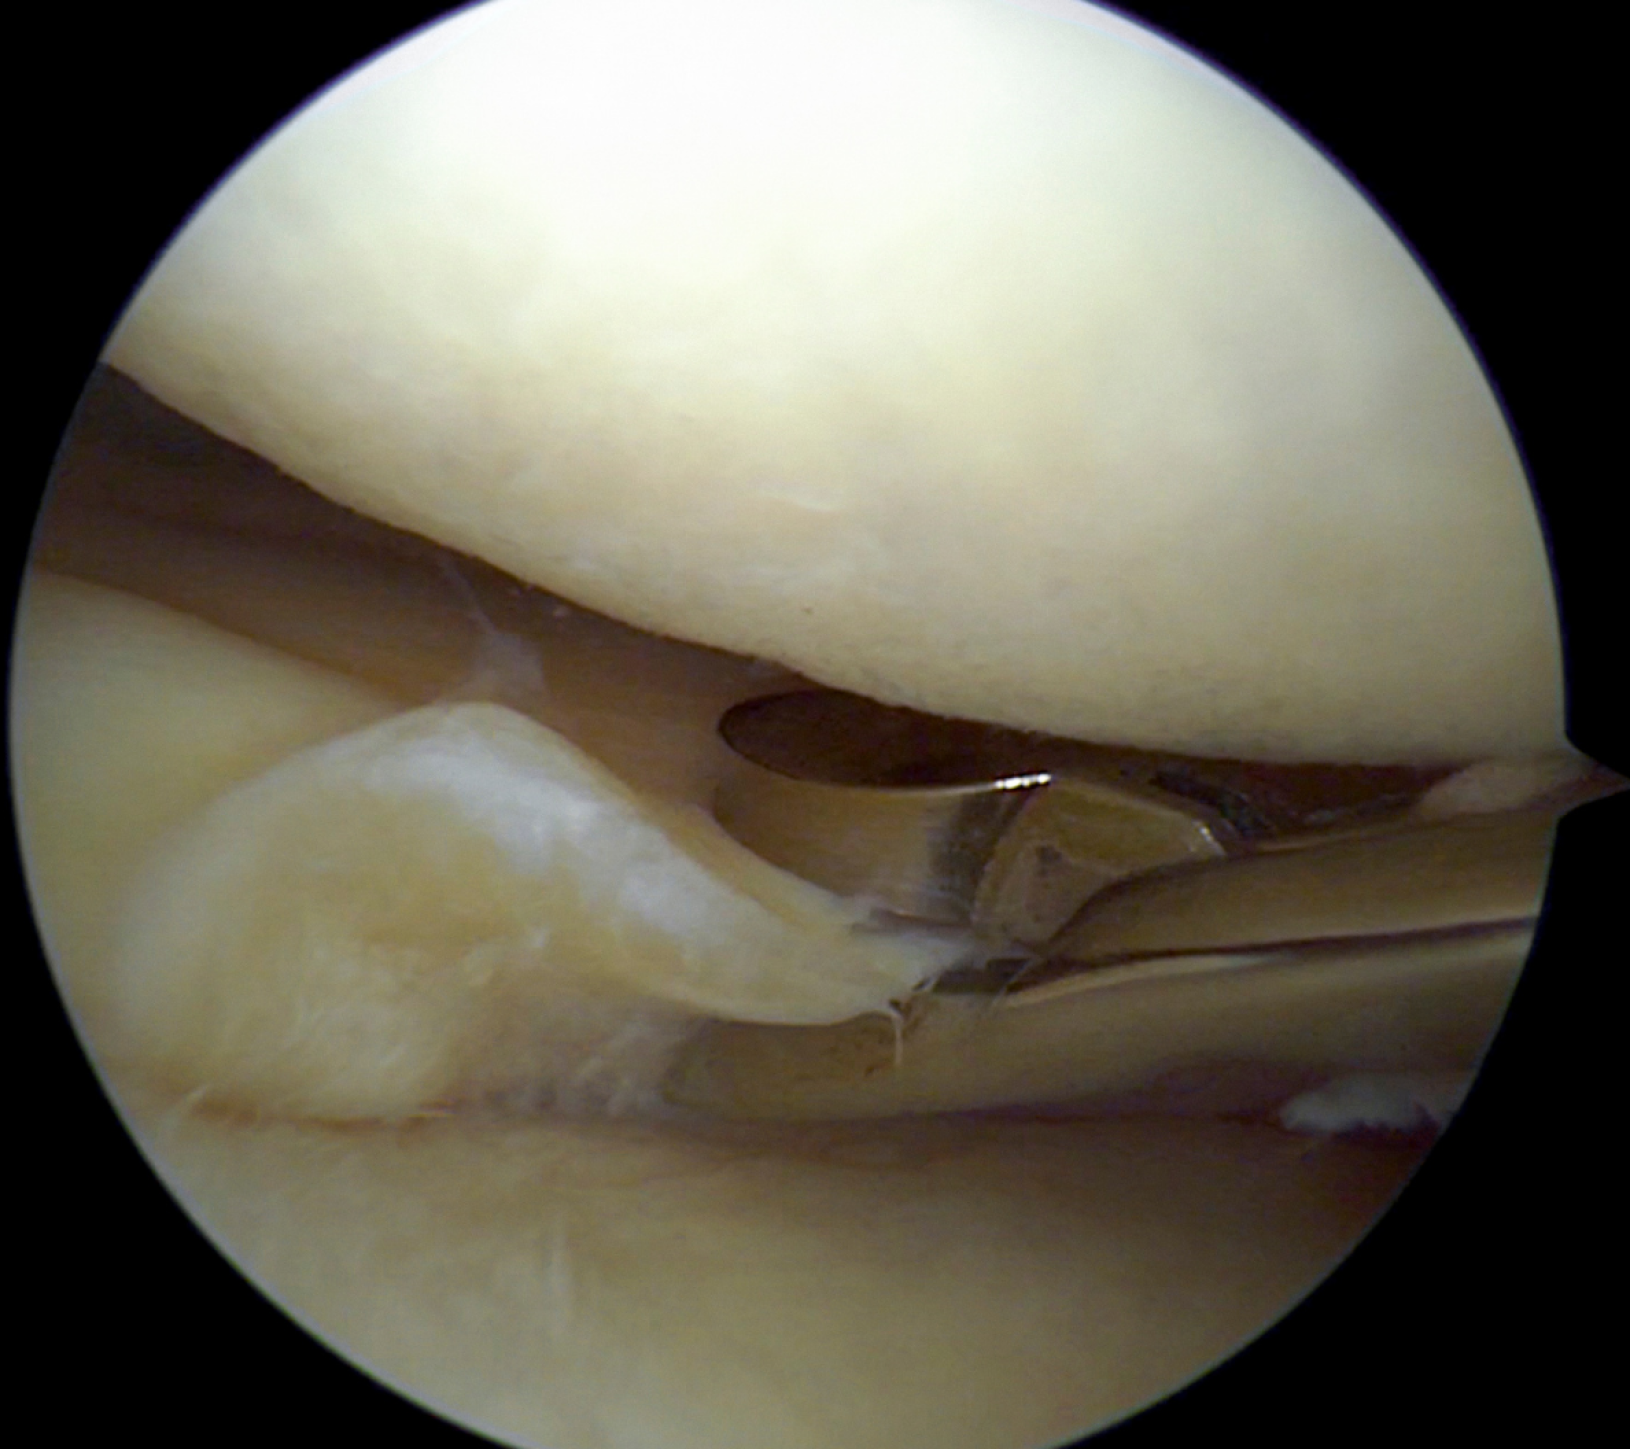

Mediante la misma es posible visualizar el interior de la articulación utilizando un instrumento denominado artroscopio, que se trata de una pequeña cámara quirúrgica.

La cámara introducida transmite una imagen en aumento, de alta calidad y en directo de los tejidos articulares.

Además de estudiar las diferentes estructuras articulares, en el procedimiento artroscópico se pueden realizar diferentes tratamientos, como puede ser la retirada de fragmentos de cartílago, curetaje de superficies articulares, o la reparación de lesiones ligamentosas entre otros.